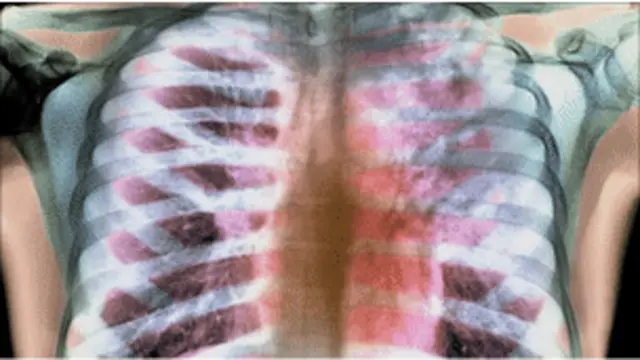

शोध में पता चला है कि क्षय रोग के जीवाणु इलाज के दौरान बचाव के लिए अस्थि मज्जा की मूल कोशिकाओं में छुप जाते हैं और बाद में फिर से प्रकट होते हैं, और यही वजह है कि लोगों में इलाज के बाद भी टीबी की शिकायतें दोबारा बड़े पैमाने पर पाई जाने लगी हैं.

हाल के दिनों में टीबी के मरीज़ ठीक होने के बाद फिर से बीमारी से ग्रसित हो गए हैं, और दोबारा उनके इलाज में बहुत दिक्क़ते आती हैं क्योंकि उनपर कई तरह के एंटीबॉयटिक का असर ही ख़त्म हो जाता है.